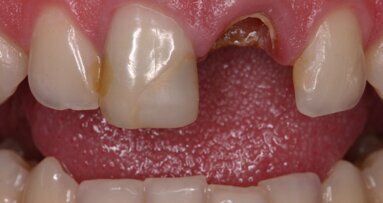

Motivo de la visita al dentista: el paciente se presentó en la sala de urgencias de nuestra clínica con dolor punzante e inflamación de la mucosa alveolar del maxilar superior izquierdo, provocados por un absceso. Además, el paciente informó sobre sensibilidad a la presión de los dientes en la región afectada. Historia clínica general y odontológica: El paciente parecía tener un buen estado de salud y no padecía ninguna enfermedad general. El examen clínico odontológico reveló que en los últimos años se le habían realizado varios tratamientos en la región posterior. En particular, existía una inflamación de la mucosa oral debida a un absceso en la pieza 25, que presentaba una fractura de la cúspide y una obturación de composite antigua.

Fig. 1: Restauración de composite antigua, fractura de la cúspide y absceso periapical en la pieza 25 con inflamación de la mucosa alveolar debida al absceso (véanse los hallazgos en la radiografía intraoral).

Diagnóstico: estado tras el tratamiento postendodóntico con poste de metal. Absceso periapical y fractura de la cúspide en la pieza 25 con inflamación de la mucosa alveolar debida a un absceso en la región afectada (Fig. 1).